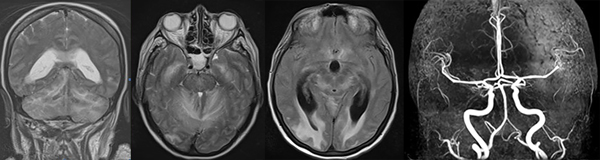

La RMN realizada de inmediato mostró edema cerebeloso y ausencia de compromiso troncal (Figura 8).

Figura 8: RMN y angioRMN: se aprecia edema cerebeloso bilateral, compromiso cerebral a nivel occipital a predominio derecho, balonización del tercer ventrículo y ausencia de oclusiones arteriales.